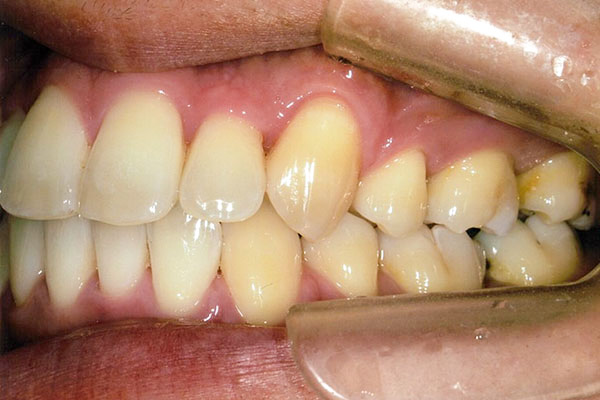

1年5ヶ月後